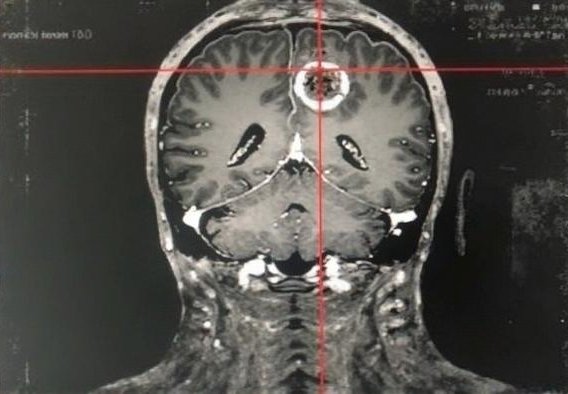

Nézze meg a képet. Egy 39 éves budapesti páciens agyi erei láthatók. Korábban ilyen állapotú ereket csak idősebb korban tapasztaltak, ma viszont sok 40 év feletti embernél előfordulhatnak hasonló problémák. A legnagyobb gond, hogy sokan nem figyelnek az első jelekre, pedig az időben felismert tünetekkel sokat tehetünk egészségünk megőrzéséért.

Agyi érrendszer felvétele — illusztráció

Illusztráció az agyi erek állapotáról — egy 39 éves budapesti páciens agyi ereinek felvétele. A szakértők szerint az ilyen korai jeleket nem szabad figyelmen kívül hagyni — minél hamarabb fordítunk figyelmet az érrendszer egészségére, annál jobbak a hosszú távú kilátások.

40 év felett az erek állapota kiemelt figyelmet igényel. Ha a fenti jelek bármelyikét tartósan tapasztalja, ne halassza el a lépéseket — minél hamarabb foglalkozik az érrendszer egészségével, annál jobbak a kilátások.